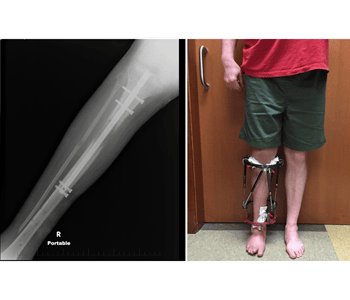

Limb Lengthening & Deformity Correction Performed by Dr. Lokesh | Eternal Orthopaedics At Eternal Orthopaedics, Dr. Lokesh offers comprehensive limb lengthening and deformity correction services for patients with limb length discrepancies, congenital conditions, post-traumatic shortening, or bone growth abnormalities. Using state-of-the-art technology and individualized planning, we help patients regain symmetry, function, and mobility. WhyLeer Más